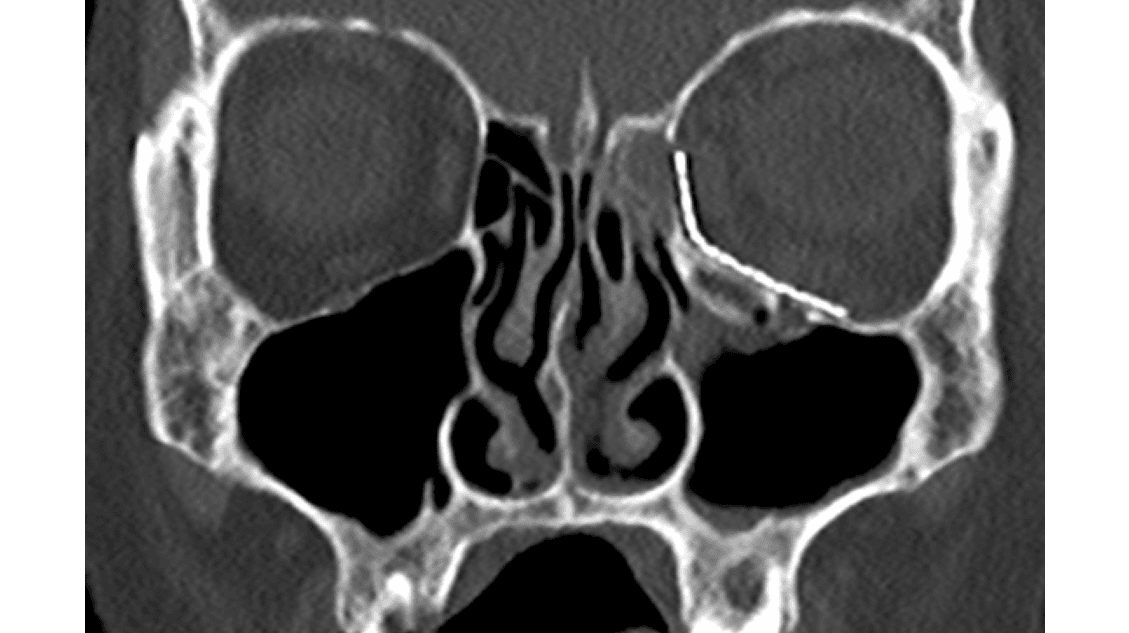

Udredning baserer sig på traumets art, klinik og billeddiagnostik [6]. Billeddiagnostikken har udviklet sig i betydelig grad, og det er nu muligt at danne 3D-rekonstruktioner samt se scanninger i både aksialt, koronalt og sagittalt snit på enhver computer med adgang til billeddiagnostik. Denne gennemgang er sammen med den kliniske undersøgelse afgørende for valg af behandling. Behandlingen af ansigtsfrakturer er enten kirurgisk eller ikkekirurgisk i form af konservativ behandling. Generelt afhænger valget af, om frakturerne er kosmetisk skæmmende eller har funktionel påvirkning såsom truet syn, dobbeltsyn, indskrænket gabeevne, ændret sammenbid eller påvirkning af følesans [5]. Desuden kan kirurgisk fiksation komme på tale af hensyn til frakturstabiliteten. Mange ansigtsfrakturer kan behandles konservativt. Hvis kirurgi er nødvendig, er der to principper, som afhænger af frakturstabiliteten. Stabile frakturer efter reponering behøver ikke osteosyntese. Ved ustabile frakturer anvendes fiksation med titaniumlavprofilerede miniplader, net og skinner eller præformede orbitabundproteser, som fikseres med små skruer, som er osseointegrerbare (Figur 1). Disse behøver ikke at blive fjernet senere hen. Dette har fuldstændig afløst tidligere tiders ståltrådscerclager, sinusballoner og eksterne fiksaturer.

Mange BOF behandles konservativt, idet symptomerne kan være yderst begrænsede. Kirurgisk behandling sker oftest med konjunktival adgang posteriort for tarsalpladen og med indlæggelse af en præformet titaniumorbitabundprotese, som fikseres til nedre orbitakant med skruer. Indgrebet udføres, når frakturen er større end ca. 1 cm2 samt ved udtalt dobbeltsyn. Ved truet syn opereres akut og ved trap-door foretages indgrebet subakut for at begrænse muskelskade [9]. Postoperativ CT viser protesens beliggenhed, og efter ca. 14 dage udføres kontrol for dobbeltsyn ved øjenlæge (Figur 3).